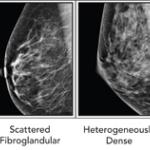

Mammography remains the standard means of screening for breast cancer. For women with denser breast tissue, the superimposition of tissue may mask early tumors even for the most observant of radiologists.

Recently, we wrote about the challenges that women with dense breasts face with mammograms — the primary tool used to screen for breast cancer.